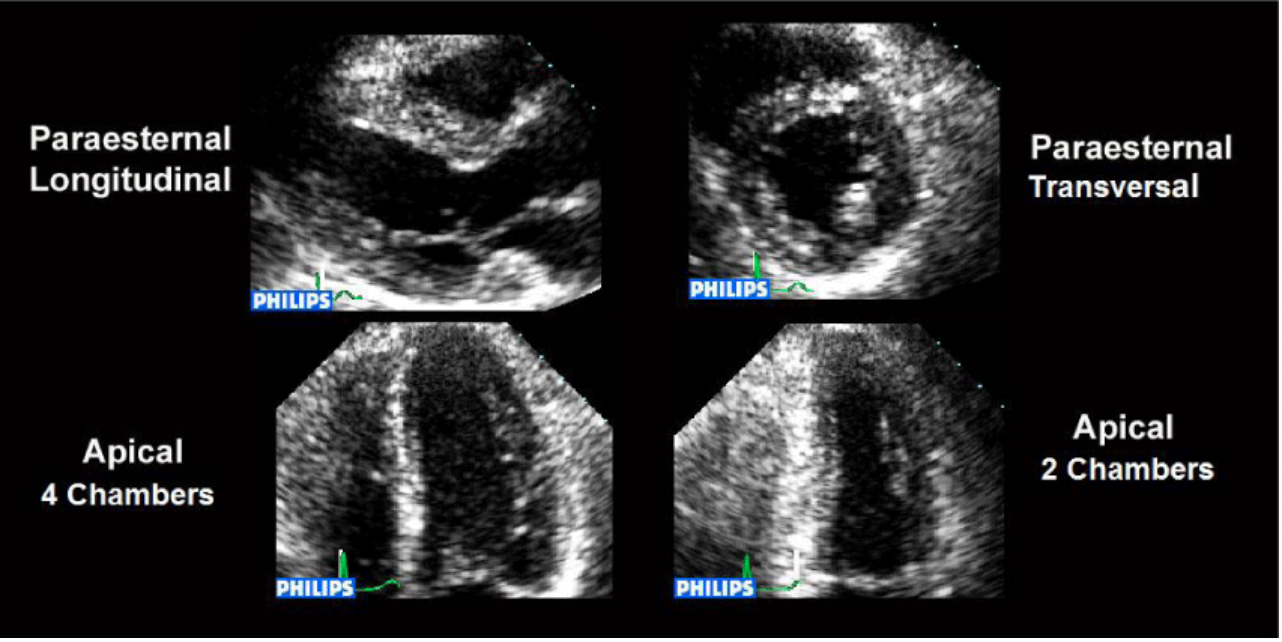

What are the views for resting images (after a baseline echo)?

PLAX

PSAX

AP-4Ch

AP-2Ch

AP-3Ch (optional)

Views demonstrating valvular color flow